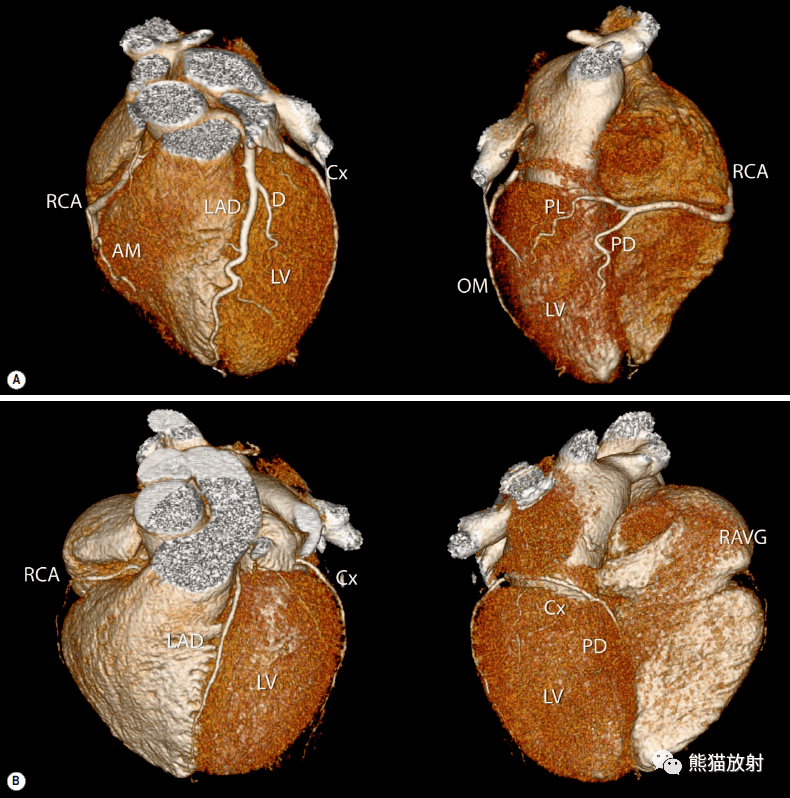

左回旋支血管示意图,右冠状动脉

心脏有三根主要的血管,分别是左前降支,左回旋支,右冠状动脉,它们分布

冠状动脉血管树解剖示意图 冠状动脉解剖 左回旋支及右冠状动脉都是在

格艾选读丨冠状动脉ct:相关概念,解剖_回旋

左回旋支分支解剖

左回旋支分支示意图

左回旋支解剖图